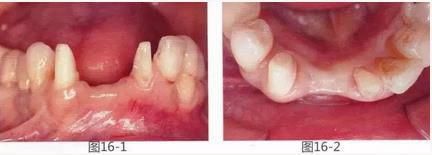

圖16-7  采集得到的結(jié)締組織瓣。

圖16-8  將上皮部分切離時(shí)。